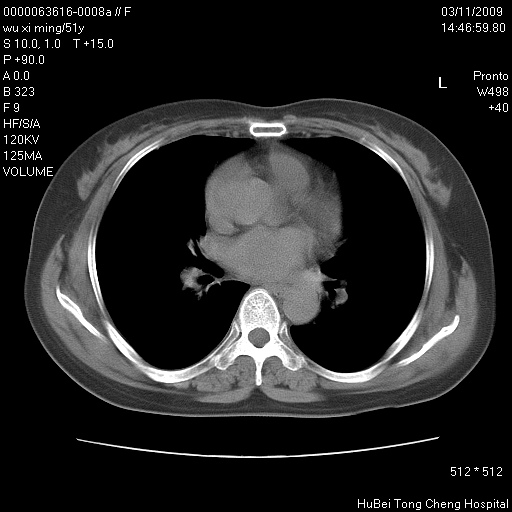

患者 女,51岁。因“胆囊炎,胆囊结石”,行常规术前胸部x线检查发现:右上肺结节病灶,建议行进一步检查。患者无咳嗽、咳痰及咯血等呼吸道症状,近期出现背部疼痛不适。

胸部ct轴位平扫(层厚10mm,螺距1.5,重建间隔10mm;部分层面:层厚3mm,螺距1.0,重建间隔3mm),图像如下:

右肺周围型肺癌伴肺内转移信胸椎转移

1、周围型肺癌。(毛刺正、血管束集征,分叶。)

集束征,胸膜牽拉征,毛刺,淺分葉高度提示ca.

右肺周围型肺癌伴肺内转移及胸椎转移。已无手术机会。